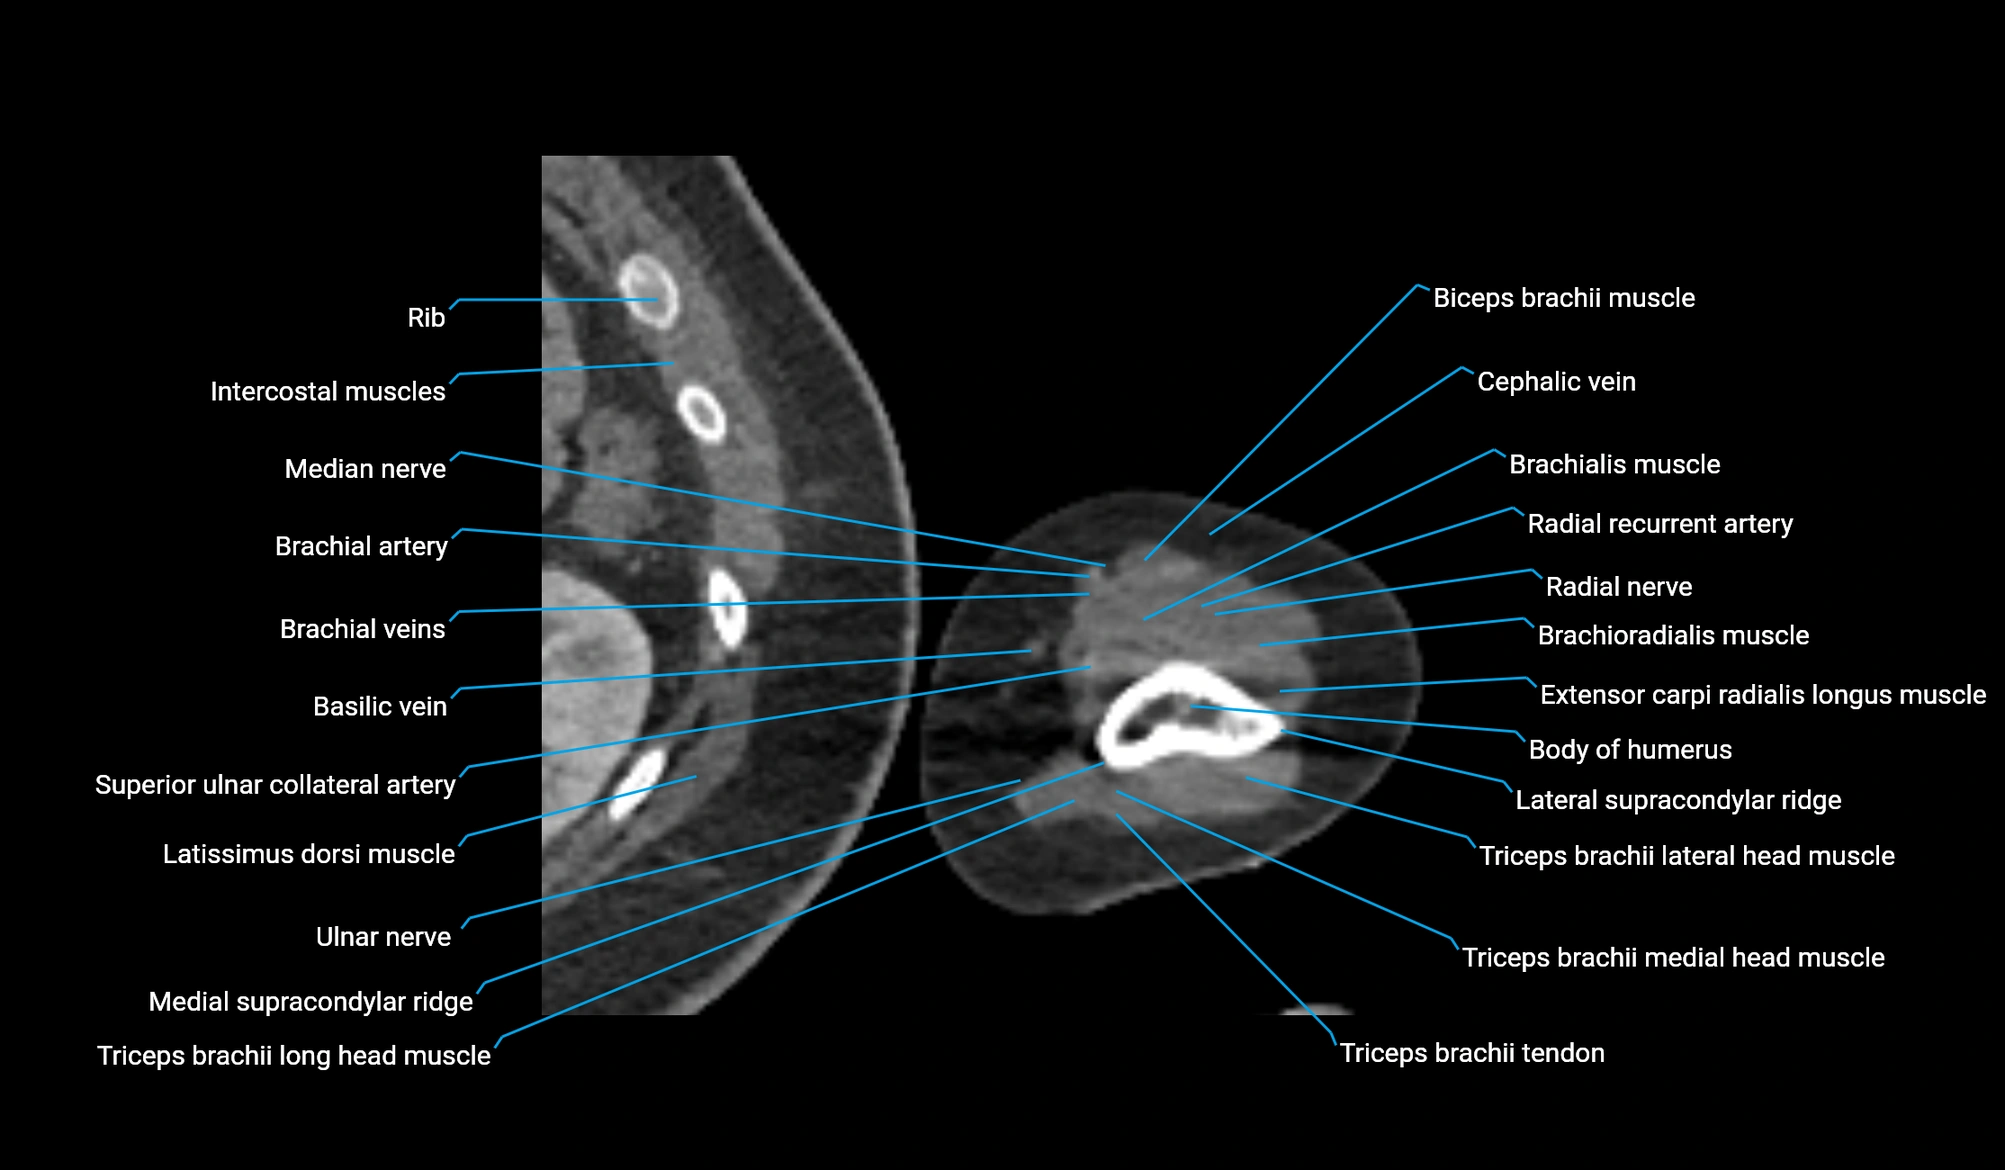

CT image